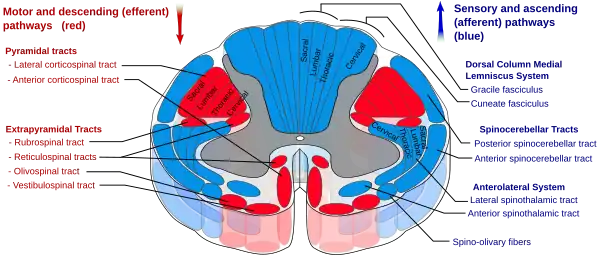

Medulla spinalis. (Extrapyramidal tracts are labeled as a group in red, at bottom left.) | |

In anatomy, the extrapyramidal system is a part of the motor system network causing involuntary actions.[1] The system is called extrapyramidal to distinguish it from the tracts of the motor cortex that reach their targets by traveling through the pyramids of the medulla. The pyramidal tracts (corticospinal tract and corticobulbar tracts) may directly innervate motor neurons of the spinal cord or brainstem (anterior (ventral) horn cells or certain cranial nerve nuclei), whereas the extrapyramidal system centers on the modulation and regulation (indirect control) of anterior (ventral) horn cells.

The extrapyramidal tracts are chiefly found in the reticular formation of the pons and medulla, and target lower motor neurons in the spinal cord that are involved in reflexes, locomotion, complex movements, and postural control. These tracts are in turn modulated by various parts of the central nervous system, including the nigrostriatal pathway, the basal ganglia, the cerebellum, the vestibular nuclei, and different sensory areas of the cerebral cortex. All of these regulatory components can be considered part of the extrapyramidal system, in that they modulate motor activity without directly innervating motor neurons.

The extrapyramidal tracts include parts of the following:[2][3]

- rubrospinal tract: Conflicts between the motor commands sent by the cerebrum and body position information provided by the proprioceptors cause the cerebellum to stimulate the red nucleus of the midbrain. The red nucleus then sends corrective commands to the spinal cord along the rubrospinal tract.

- reticulospinal tract: connects the reticular system, a diffuse region of gray matter in the brain stem, to the spinal cord. It also contributes to muscle tone and influences autonomic functions.

- lateral vestibulospinal tract: Connects the brain stem nuclei of the vestibular system with the spinal cord. This allows posture, movement, and balance to be modulated on the basis of equilibrium information provided by the vestibular system.

- tectospinal tract: This tract projects from the midbrain to the spinal cord and is important for postural movements that are driven by the superior colliculus.